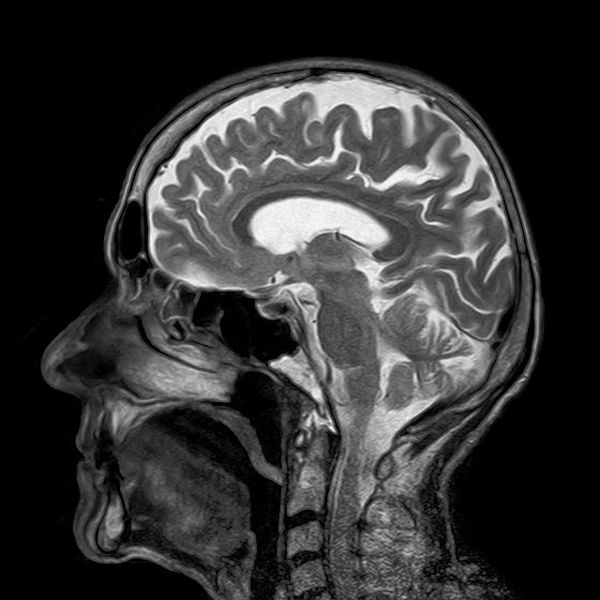

Cómo la ketamina puede cambiar el cerebro para combatir la depresión

Por Maria Cohut Una nueva investigación en ratones, apoyada por los Institutos Nacionales de la Salud, muestra cómo la ketamina puede alterar los circuitos...